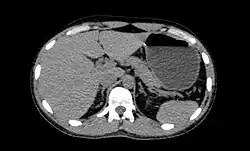

CT is an accurate technique for diagnosis of abdominal diseases like Crohn's disease,[69] GIT bleeding, and diagnosis and staging of cancer, as well as follow-up after cancer treatment to assess response.[70] It is commonly used to investigate acute abdominal pain.[71] Non-enhanced computed tomography is today the gold standard for diagnosing urinary stones.[72] The size, volume and density of stones can be estimated to help clinicians guide further treatment; size is especially important in predicting spontaneous passage of a stone.[73]